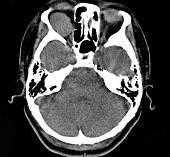

问题 41岁女性,右眼胀痛、眼球外突3月余,体检,发现低头时右侧眼球外突加重,CT检查如图所示,请选择最可能诊断()

选项 A.右侧眶内血管瘤 B.右侧眶内炎性假瘤 C.眼型格氏病 D.右侧眶内神经鞘瘤 E.右侧眶内皮样囊肿

答案 A